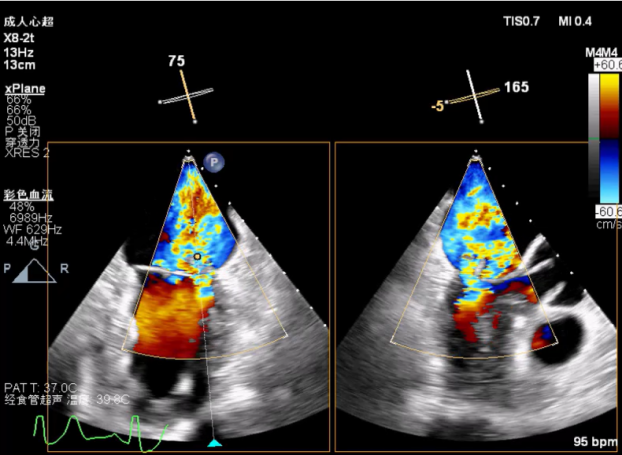

X-plane:下夹子尝试捕获2区脱垂瓣叶

3D证实夹子外侧残余脱垂及瓣叶裂空

将第二个夹子置于第一个夹子外侧并调整Orientation

成功抓捕外侧残余脱垂区域瓣叶

第二个夹子外侧残余小束分流,宽3.7mm

3D视图两个夹子近似并排排列,第二个夹子外侧小残余脱垂,瓣叶裂孔已不明显